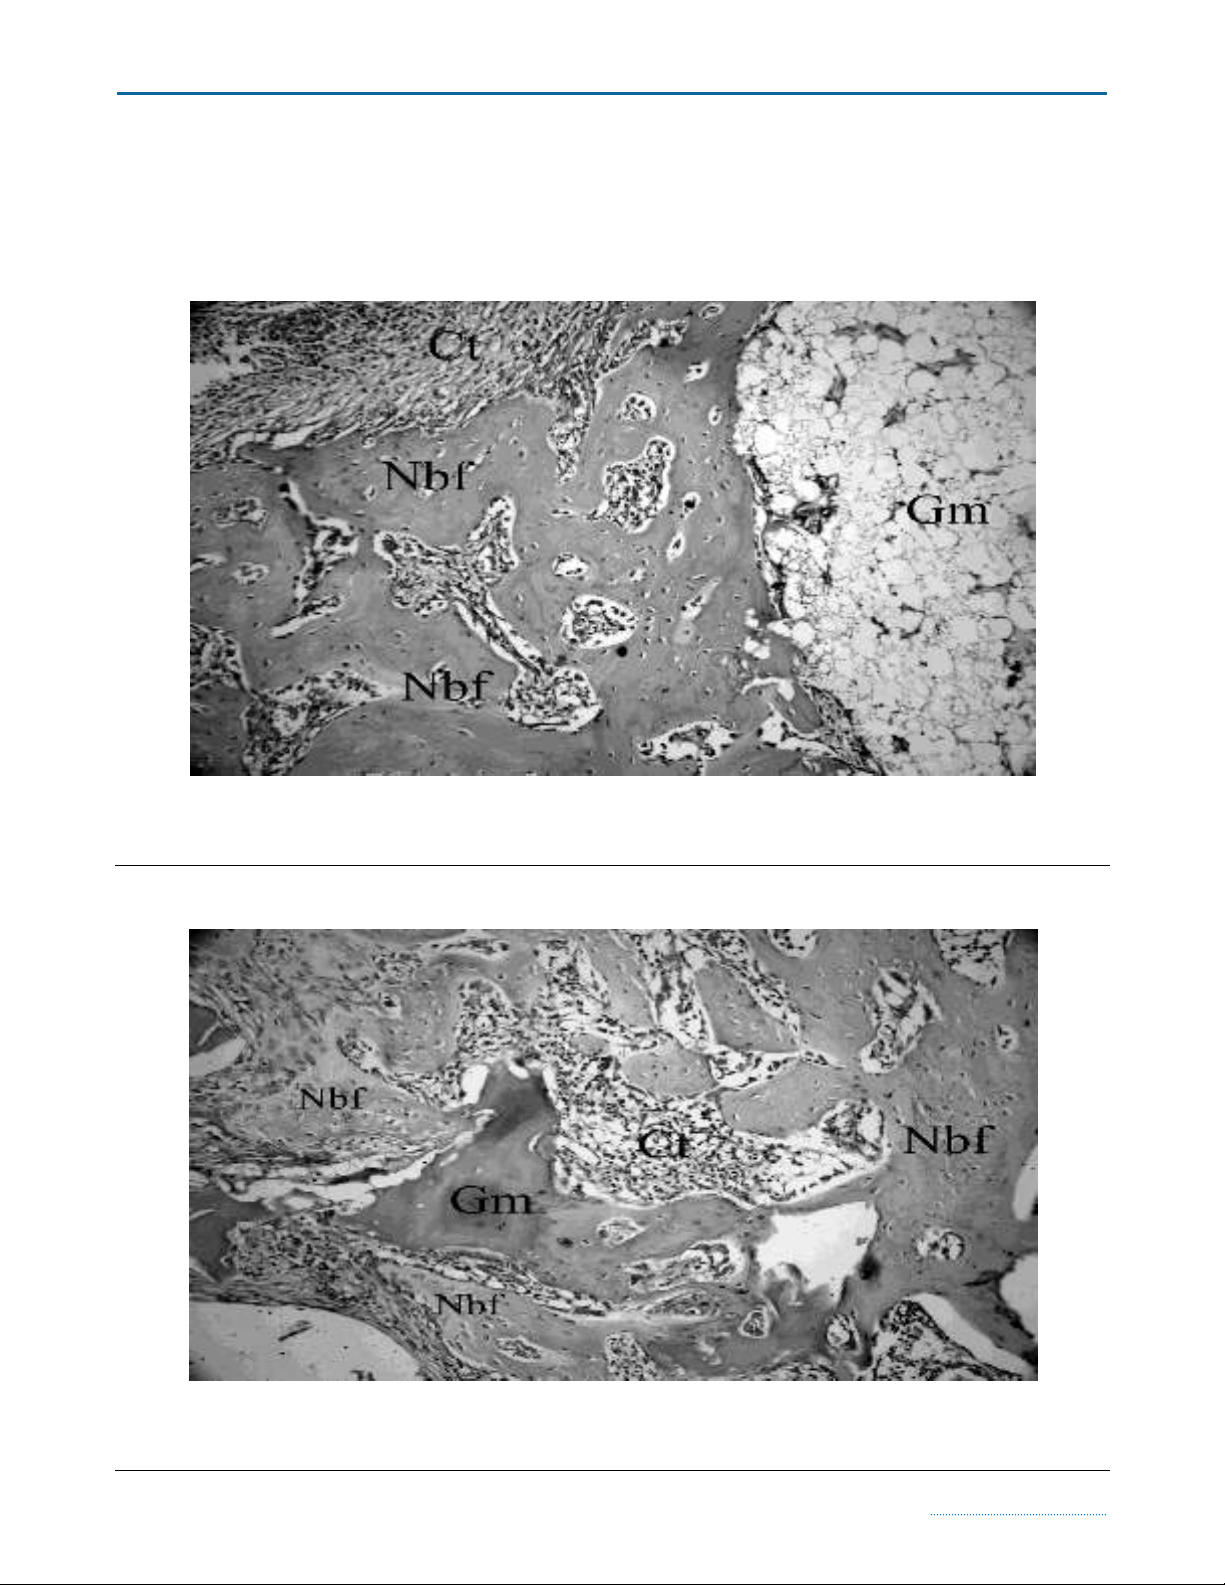

Figure 2 New bone formation and residual graft particles were observed in the histological section taken from the β-TCP

group with adjunctive HBOT at four week time point (H&E×200) (Nbf; New bone formation, Gm; Graft material, Ct;

Connective tissue).

Figure 3 CPCBB graft material which is gradually resorbing and resembles the necrotic bone can be seen in the middle of

this slide. This section has been taken from the CPCBB + HBOT group which was sacrified at four week time point

(H&E×200) (Nbf; New bone formation, Gm; Graft material, Ct; Connective tissue).